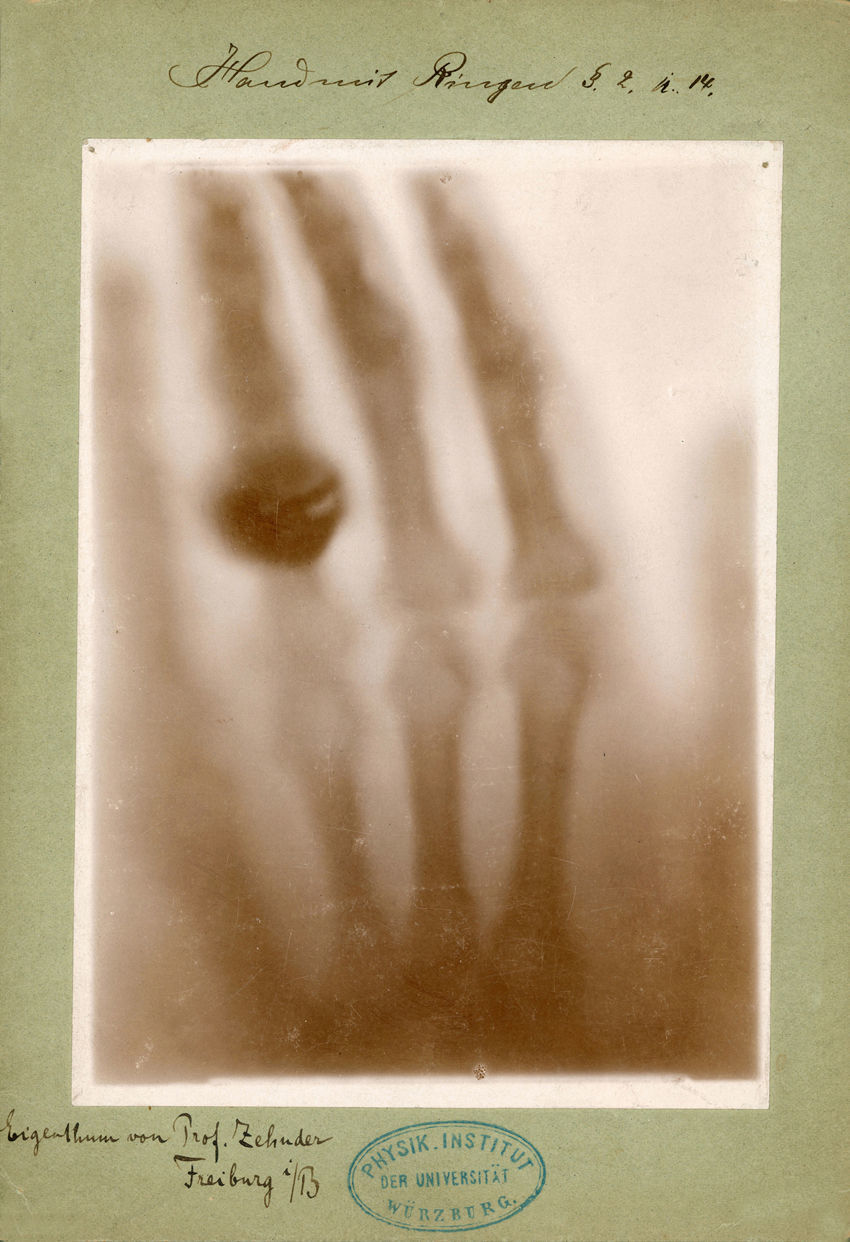

La primera detección de rayos X ocurrió en un laboratorio y de forma accidental. En 1895, el físico alemán Wilhelm Conrad Röntgen se encontraba experimentando con tubos de rayos catódicos; éste consiste en un recipiente de vidrio vacío donde se hace correr un haz de electrones que enciende una capa fluorescente. Para que no se escapara nada de la luz fluorescente, envolvió el tubo con cartón. Röntgen notó que una pantalla cercana al tubo comenzó a brillar, es decir, unos rayos invisibles atravesaron el cartón y ahora iluminaban la pantalla. Como Röntgen no sabía qué eran esos rayos, les llamó rayos X, usando la X para indicar lo desconocido.

Hoy sabemos que esos rayos X se emiten cuando electrones muy energéticos chocan contra una placa metálica y liberan energía al desacelerarse o al arrancar electrones de los átomos de la placa. Röntgen le pidió a su esposa Bertha que colocara su mano entre el tubo y una placa fotográfica y así obtuvo la primera radiografía de la historia (Fig. 2). Por el descubrimiento de los rayos X, Röntgen se convirtió en el primer galardonado con el Premio Nobel de Física en 1901.